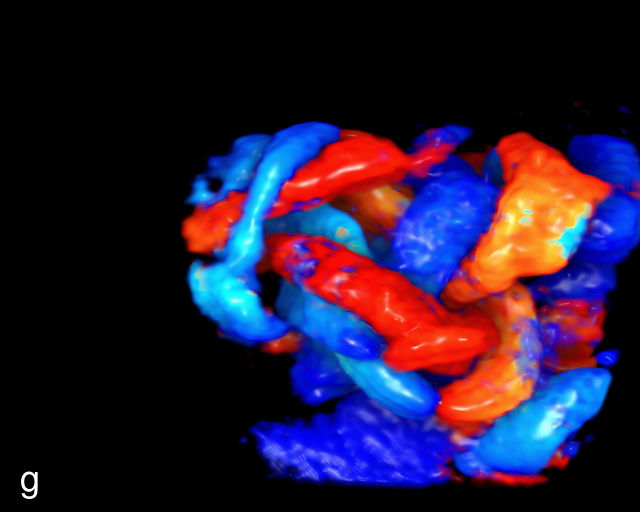

UMBILICAL CORD

Normal anatomy, development and ultrasound appearance

The umbilical cord serves as the lifeline connecting the fetus to the placenta. It arises from the midportion of the fetal abdomen and typically inserts into the center of the placenta (Figure 16). The average length of the umbilical cord is approximately 55 cm (22 inches).185 It contains three vessels: two arteries, which originate from the fetal left and right internal iliac arteries, and one vein, collectively referred to as a three-vessel cord.

Normal appearance of the umbilical cord with two umbilical arteries and a single vein. (a–c) Cross-section of the umbilical cord on grayscale (a,b) and power Doppler (c) ultrasound. In the normal cord, three vessels are visible: a larger umbilical vein and two smaller umbilical arteries. This characteristic appearance is often referred to as the 'Mickey Mouse' sign, the larger circle (umbilical vein) representing Mickey’s face while the smaller circles (arteries) form his ears. (d–g) Grayscale (d) and color Doppler (e–g) images of transverse section of the lower fetal abdomen showing the two umbilical arteries diverging around the fetal bladder. (h) Longitudinal ultrasound view with color Doppler of a normal umbilical cord showing three vessels present in each coil: two arteries with flow in one direction and a single vein with flow in the opposite direction.

The umbilical vein carries oxygenated blood from the placenta to the fetus, while the two umbilical arteries return deoxygenated blood and waste products from the fetus to the placenta for exchange with the maternal circulation. These vessels are surrounded and protected by Wharton’s jelly, a specialized connective tissue derived from the extraembryonic mesoblast, which cushions the vessels and prevents compression. As the umbilical cord approaches its placental insertion, the two arteries form Hyrtl’s anastomosis, a connection that helps equalize blood flow between the arteries.

At a minimum, the mid-trimester ultrasound should include identification and documentation of the umbilical cord's fetal and placental insertions, as well as the number of cord vessels.66,186,187 In a transverse grayscale section of the cord, the two umbilical arteries can be visualized alongside the larger, thinner-walled umbilical vein, creating a characteristic ‘Mickey Mouse’ appearance (Figure 16a–c). Additionally, in a transverse section of the lower fetal abdomen, the umbilical arteries are seen encircling the fetal bladder. This can be seen on grayscale ultrasound and confirmed with color flow Doppler (Figure 16d–g).

A normal umbilical cord is helical, with an average of 2.1 coils per 10 cm of cord length.188,189 The majority of umbilical cords exhibit a leftward (counterclockwise) twist, with a left-to-right twist ratio of approximately 7 : 1, making the rightward (clockwise) twist significantly less common.185,190,191 This twisting structure is believed to provide additional protection against compression and kinking during pregnancy.192

Abnormal cord coiling

The umbilical cord coiling index (UCI) is defined as the number of complete vascular coils per cm of cord, with a normal UCI averaging around 0.2.185,191 A hypocoiled cord is typically defined as having an UCI of less than 0.2, or below the 10th percentile, with approximately one coil per 10 cm of cord (Figure 18a–c). In contrast, a hypercoiled cord has an UCI greater than 0.3, or above the 90th percentile (Figure 18d; Video 9). It is estimated that hypocoiling of the cord occurs in between 4% and 15% of pregnancies.185,191